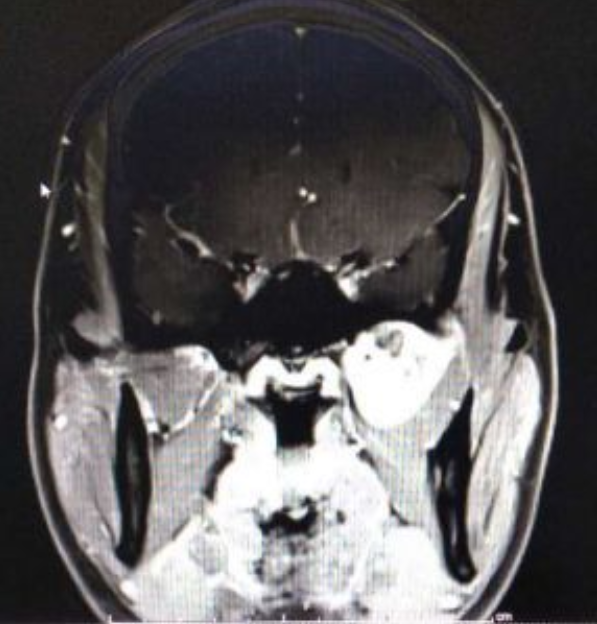

术后第一天CT显示

术前术后中颅底对比

术后增强核磁显示